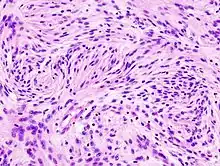

Astrocytomes anaplasiques

L'astrocytome anaplasique est une tumeur cérébrale maligne caractérisée par une croissance diffuse, une densité cellulaire accrue et des figures de division nucléaire. Elle est issue d'une population cellulaire spécifique du système nerveux central, les astrocytes. Selon la classification OMS des tumeurs du système nerveux central, la tumeur correspond à une tumeur de grade III.

En règle générale, les patients atteints d'astrocytome anaplasique présentent des crises d'épilepsie, des déficits neurologiques focaux, des maux de tête et des changements de personnalité. L'âge moyen des patients est de 45 ans. L'imagerie par résonance magnétique montre généralement une lésion massive avec un signal de contraste accru, qui peut aussi être plus faible. Le diagnostic repose sur l'examen histologique de la lésion par biopsie ou résection chirurgicale.

Un pronostic plus sombre peut être associé à un âge avancé, à une mauvaise condition physique et à des dommages neurologiques importants. En général, le résultat thérapeutique est meilleur avec une exérèse chirurgicale complète (traitement standard) sans augmentation des déficits neurologiques. La radiothérapie est la norme car il a été démontré qu'elle augmente le temps de survie. Le rôle de la chimiothérapie est controversé.